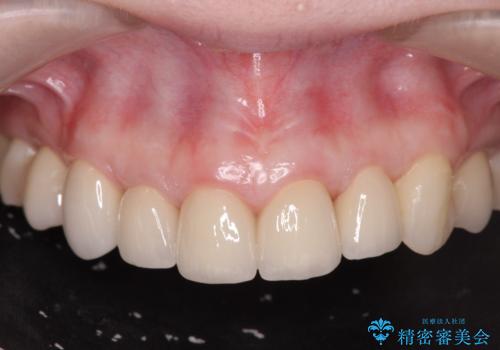

[ 歯肉縁下カリエス ] 歯周外科を行い、歯を残す

![[ 歯肉縁下カリエス ] 歯周外科を行い、歯を残すの症例 治療後](https://seimitsushinbi.jp/wp/wp-content/uploads/2023/01/fc11ac5ecfd3722f9c91e063fe42c4f3-500x350.jpg?v=1673602360)